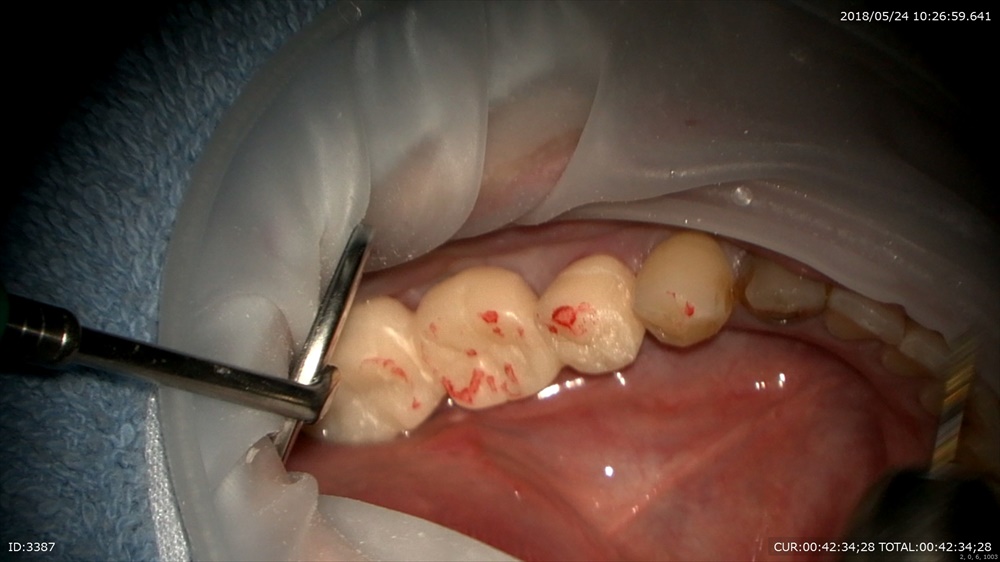

仮歯を作成

高さチェック

研磨して